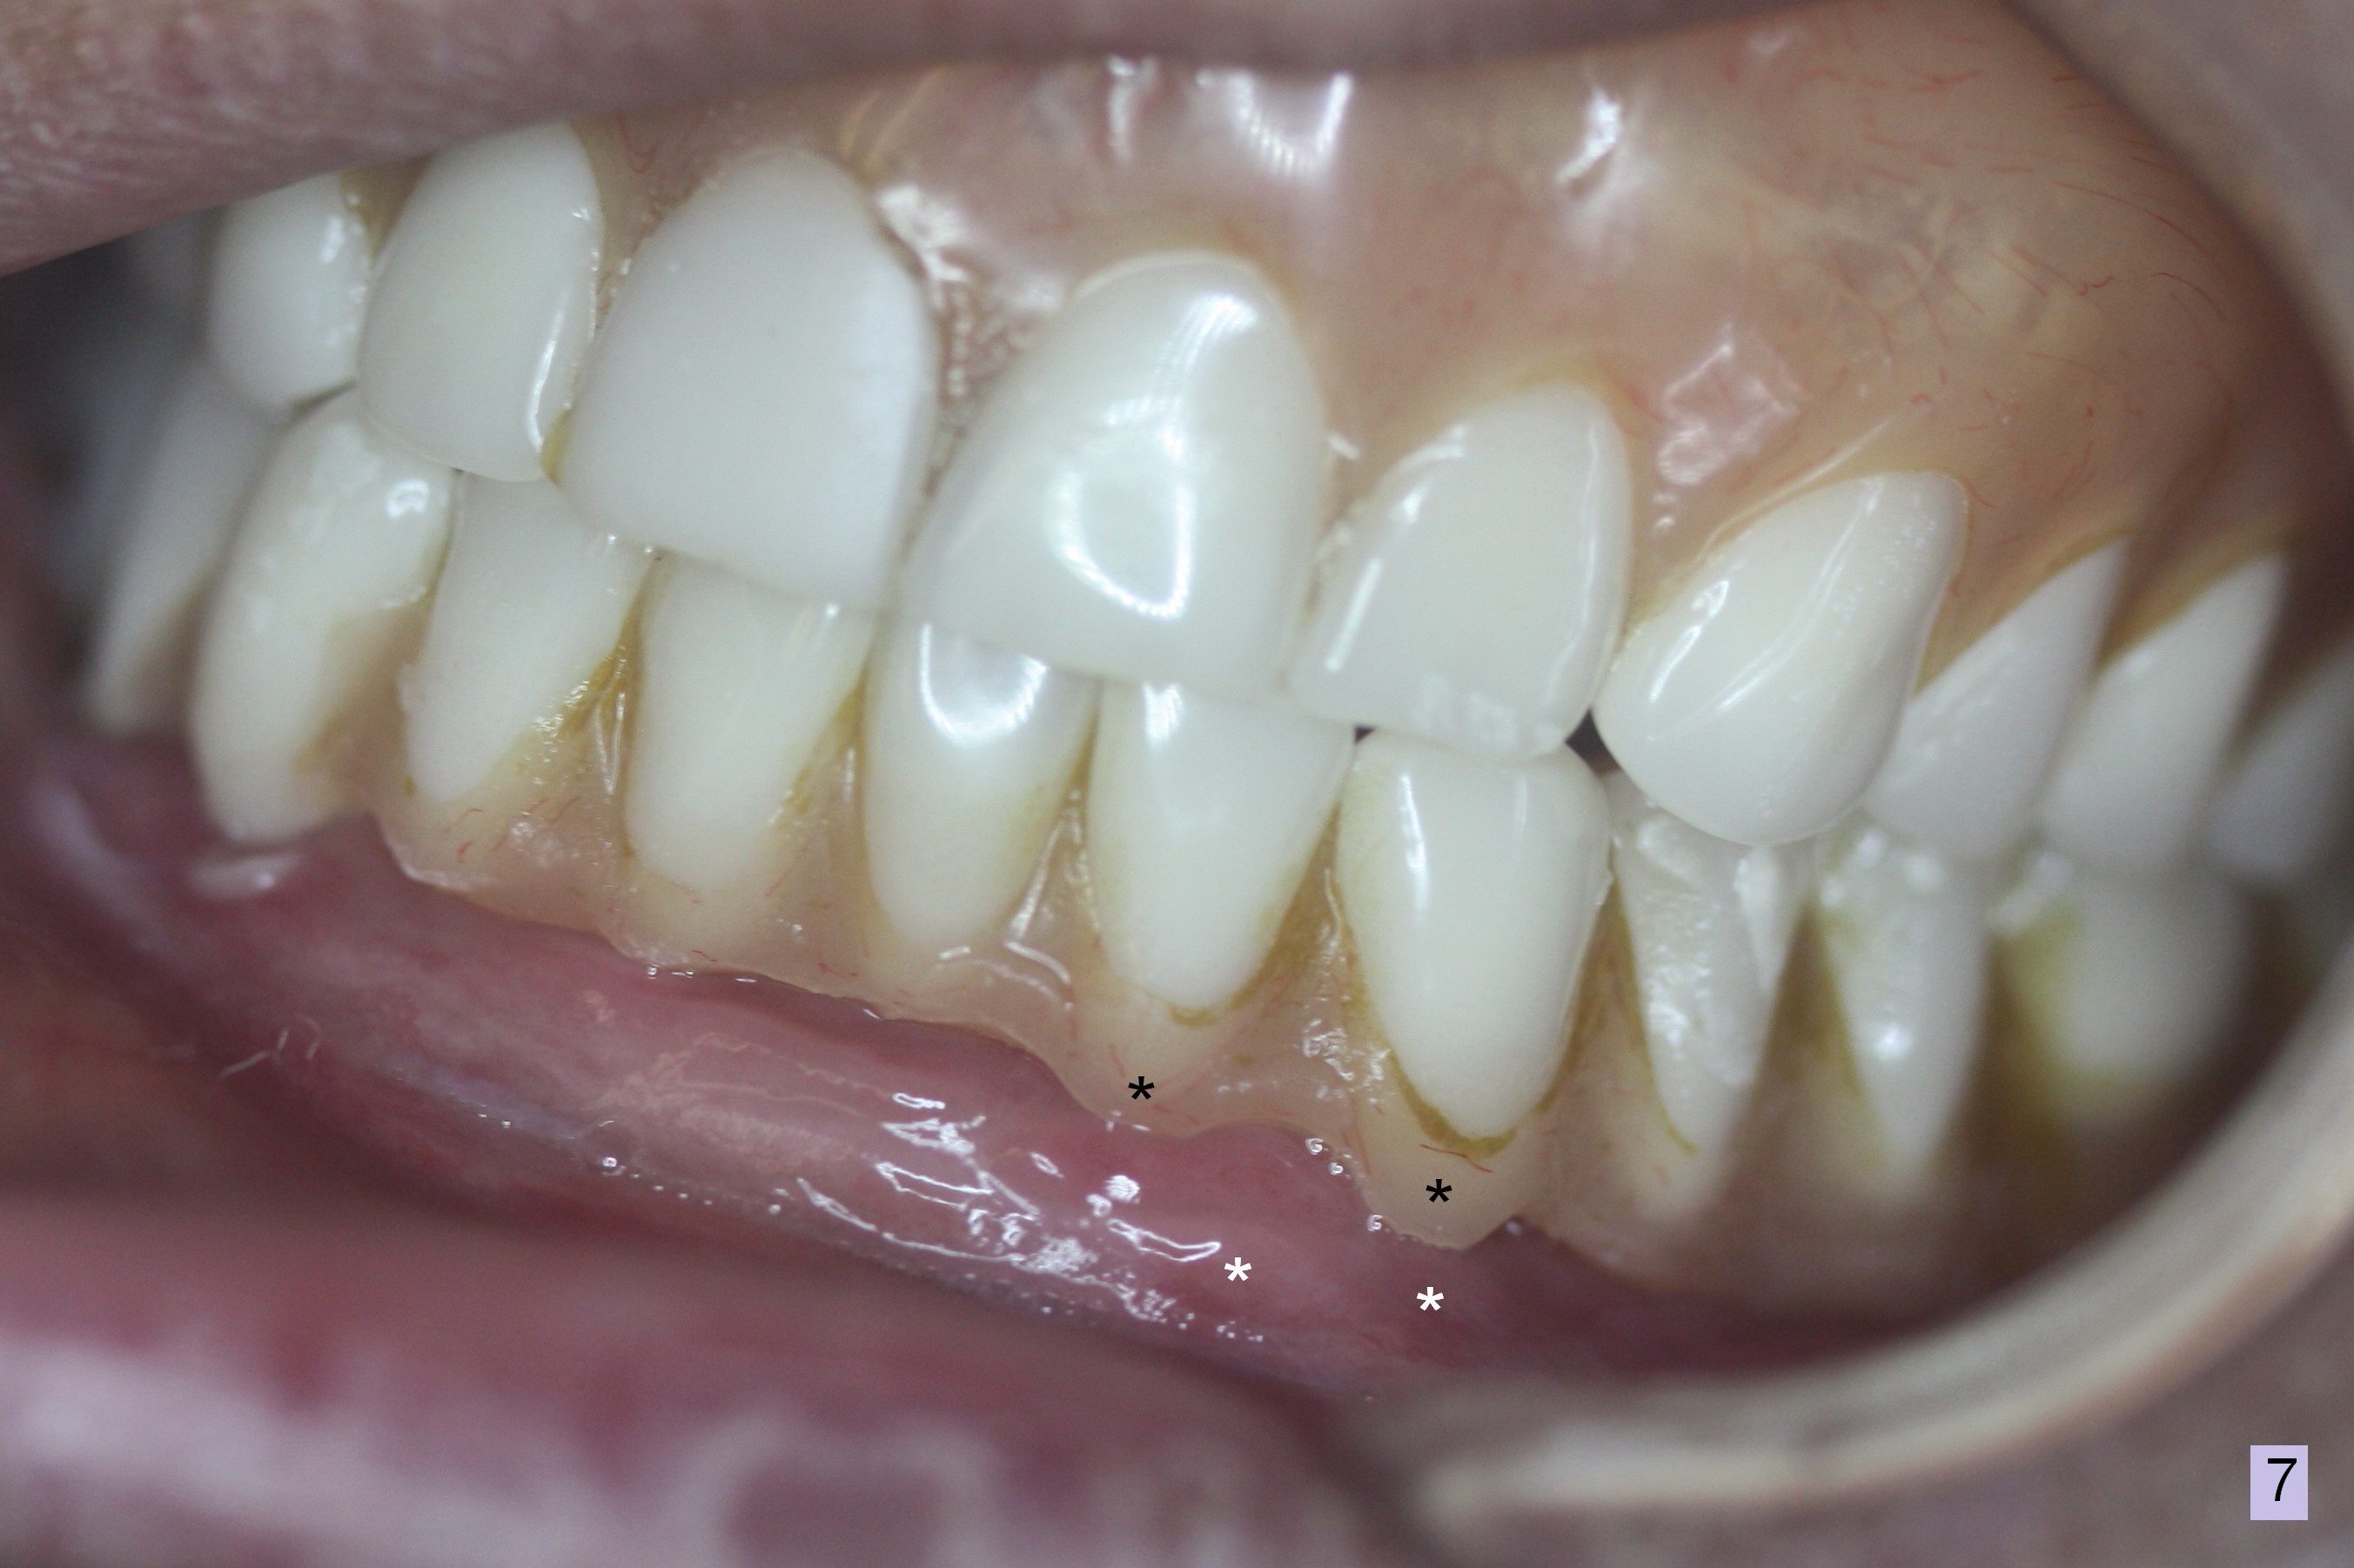

Preop photo shows that the lower lip is protrusive (Fig.1), because the lower complete denture (CD) is in cross bite (Fig.3). When the upper and lower CDs are removed, the upper and lower lips are retrusive (Fig.2). Use a modified CT scan stent to start osteotomies at the sites of the canine and the 1st premolar (Fig.4). In fact the right ones are more distal than planned. As expected, four of 3.8x8 mm implants are placed with insertion of 3.9 mm ball abutments with 2 mm cuff (Fig.5). The lingual plate at the site of #21 perforates apically when a 2.7 mm drill is being used. The defect is repaired with collagen plug and autogenous bone and Osteogen prior to implant placement. There is no postop sublingual edema or paresthesia. With trimming of the lower CD (especially the posterior border), the four implants/ball abutments appear to help establish normal overjet with immediate improvement of the facial profile (Fig.6,7 (3 days postop)). The border of the denture flange is trimmed (Fig.7 black *) to avoid contacting the tender hyperplastic tissue (white *). Further trimming may be necessary, which has been accomplished. A month later, three more implants are placed in the mandible.